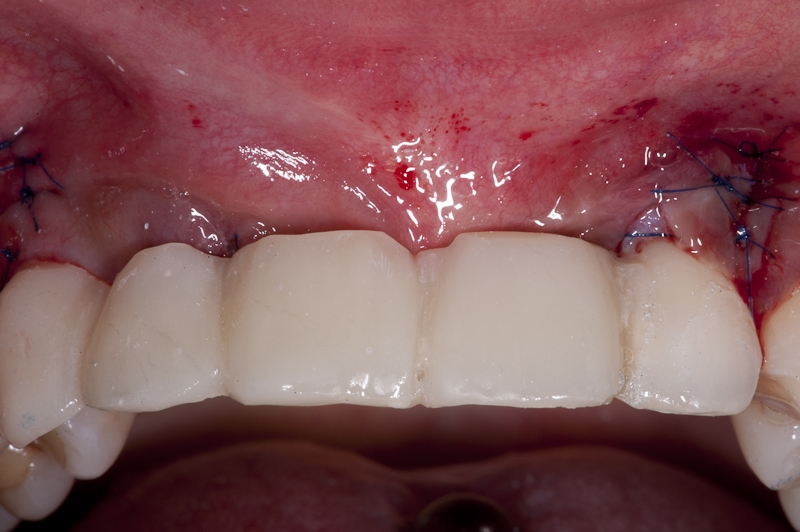

15/17 - Situation after sutures removal and healing period of two weeks

Block augmentation with maxgraft® block & mucoderm® - Dr. K. Chmielewski